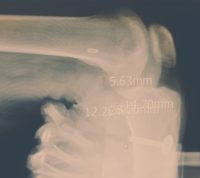

경찰청, 양의사 1명과 중개인 2명 구속 [한의신문=김대영 기자] 병원 중개인으로부터 건당 30~50만원을 받고 허위내용의 영구후유장애 진단서를 발급한 양의사 3명과 피보험자 알선 중개인 3명, 허위진단서로 보험금을 편취한 피보험자 84명 등 90명이 검거됐다. 경찰청 지능범죄수사대는 군 특수부대 전역자들이 주축이 된 후유장해보험 사기사건과 관련해 이들을 추가 입건하고 보험중개인에게 20억원을 벌게 해 준다며 온갖 개인 심부름을 시킨 양의사와 중개인 2명을 구속했다고 지난 16일 밝혔다. 경찰청에 따르면 정형외과 의사 A씨는 지난 2013년 1월부터 지난 2015년 9월까지 허위진단서 발급 중개인 D씨가 소개한 피보험자 39명에게 1인당 30~50만원을 받고 부상의 정도가 경미함에도 발목 등을 잡아 당겨 순간적으로 늘린 상태에서 엑스레이 사진을 촬영하거나 각도기를 사용하지 않고 마음대로 운동 범위를 기재하는 방법으로 영구후유장애진단서를 발급했다. 특히 의사 A 씨는 D씨에게 20억원을 벌게 해 주겠다고 현혹해 운전기사 역할 및 각종 심부름(치킨, 떡볶이, 물티슈, 로또, 커피 등의 구입과 배달)을 시켜온 것으로 드러났다. 피보험자들은 이를 근거로 보험사로부터 보험금 약 11억2000만원을 수령하고 중개인 D씨는 수수료 명목으로 피보험자로부터 1억3000만원을 수수했다. 같은 수법으로 정형외과 의사 B 씨는 허위진단서 52건을, 정형외과 의사 C씨는 허위진단서 7건을 발급해 보험사로부터 보험금 17억5000만원과 2억2000만원을 수령했다.